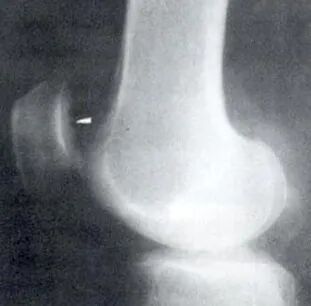

X线片:膝关节正、侧位及髌骨切线位

早期无异常;晚期可因软骨大部磨损,髌骨与股骨髁部间隙变窄、毛糙,关节对合不良,髌骨和股骨髁部边缘可有骨质增生。

• X线检查:髌骨切线位ⅹ线片对诊断髌趿排列乱及股骨髁发育不良具有十分重要的诊断价值,是髌骨软化症病因诊断常用方法。

X线:早期X线表现可无异常,晚期可见骨赘形成,髌股关节间隙狭窄、毛糙、关节对合不良。

膝关节屈曲20度摄髌股关节轴位片,观察股骨内外侧髁前面切线与髌骨外侧关节面切线的交角,即外侧髌股角Laurin角),正常应开向外侧,而异常的开向内侧。即髌骨外翻外移。